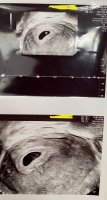

Fra TUL i går. Står 6+5 på ene bildet men etter mine egne beregninger så er jeg 6+3 i dag (6+2 i går da bildet ble tatt) :) Lille bønne :Heartpink Hjertebank på linjen nederst!

Såå koselig, ja, det er helt spinnvilt. Jeg ble rett og slett målløs da jeg lå der og ikke minst da jeg fikk høre hjertet slå. Nesten vanskelig å ta innover seg... Det sykeste var egentlig å se hvor "mye" som hadde skjedd fra forrige TUL som var gjort mindre enn en uke før, legger ved bilde her. At det kan vokse så mye på bare noen dager – og se forskjellen i hjertebank!